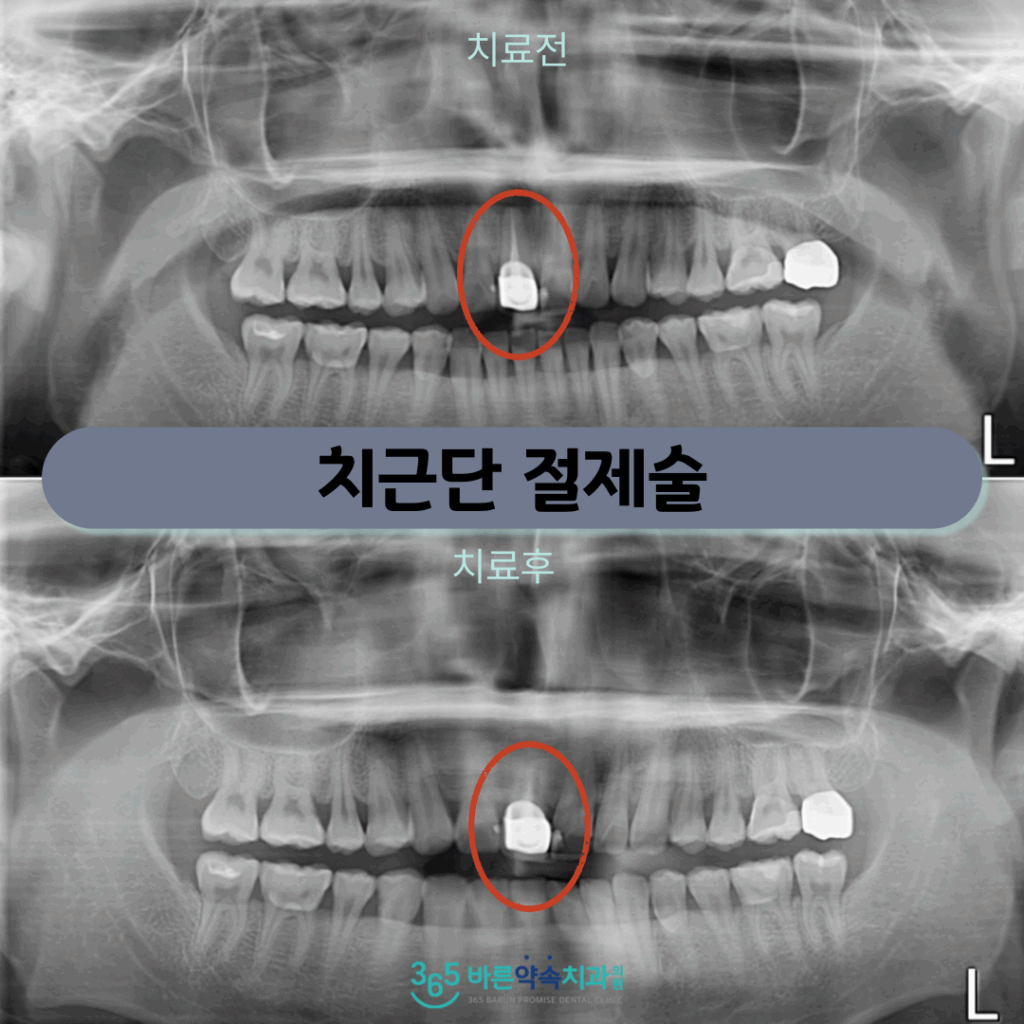

오늘은 위턱 앞니의 불편감으로 인해

망원동치과 356바른약속을 찾아주신

환자분의 사례를 소개해 드리겠습니다.

오늘 소개해 드릴 환자분께서는

20대 남성분으로

위턱 오른쪽 첫 번째 앞니(#11)

주변 잇몸이 붓고 불편감으로 인해

치아 검진을 위해

본원으로 내원해 주셨는데요.

정밀한 검사를 위해

파노라마 사진을 촬영해 보았더니

위턱 오른쪽 첫 번째 앞니(#11)의

뿌리 끝에 염증이 생긴 것을

확인할 수 있었습니다.

예전에 신경치료를 받고

보철물 수복까지 마무리된 치아이지만

현재 뿌리 끝 치근단 부위에

염증이 생긴 것인데요.

치근단 절제술 후 1주일 정도 뒤

실밥을 제거해 드렸으며

잇몸뼈 회복 상태를 확인하기 위해

파노라마와 3D CT를 촬영해 보았더니

염증이 깨끗하게 제거가 되었고

뿌리끝이 단단히 메워져 있는 것을